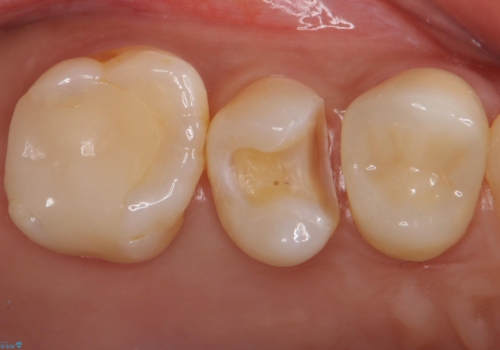

- 銀の詰め物を白くしたいとのことで来院されました。

セラミックインレーでの治療を行いました。